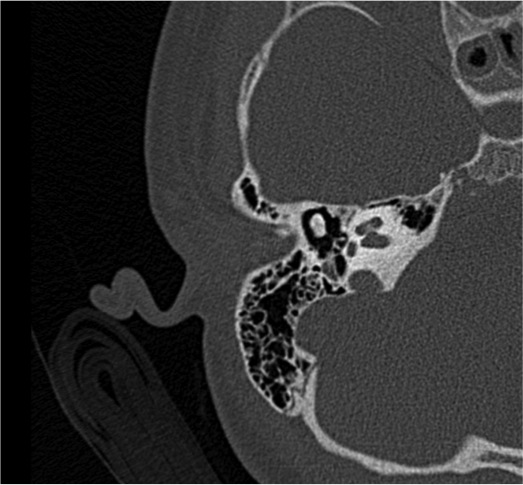

In terza giornata vengono eseguiti ulteriori approfondimenti diagnostici quali RM encefalo, angio-TC e TC delle rocche petrose che confermano un quadro di sofferenza cerebrale diffusa con coinvolgimento flogistico di aree cerebrali multiple (temporale, fronto-parietale, occipitale, emisferi cerebellari e nuclei della base), e otomastoidite con erosione delle pareti ossee delle celle mastoidee (Figura 1 e Figura 2). I tracciati EEG seriati hanno documentato un peggioramento progressivo, fino al riscontro di assenza di attivit� elettrica cerebrale in sesta giornata di ricovero.

Figura 2. RM dell'encefalo: otomastoidite con erosione delle pareti ossee delle celle mastoidee.